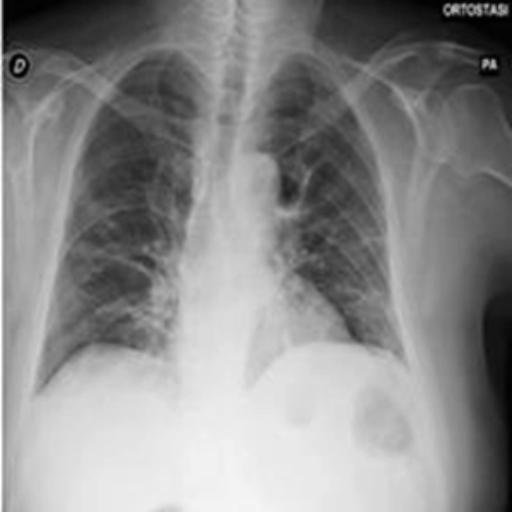

The dataset chosen in this paper is an open-source dataset, the dataset is selected from the open-source database, the database contains 150 lung X-ray images and their corresponding 150 masks, and we select four of them for presentation, the results are shown as follows, the four images in the first row are the original images of the lung X-ray, and the images in the second row in the corresponding position are their corresponding masks, as shown in Fig. 1.

Figure 1. Partial data.